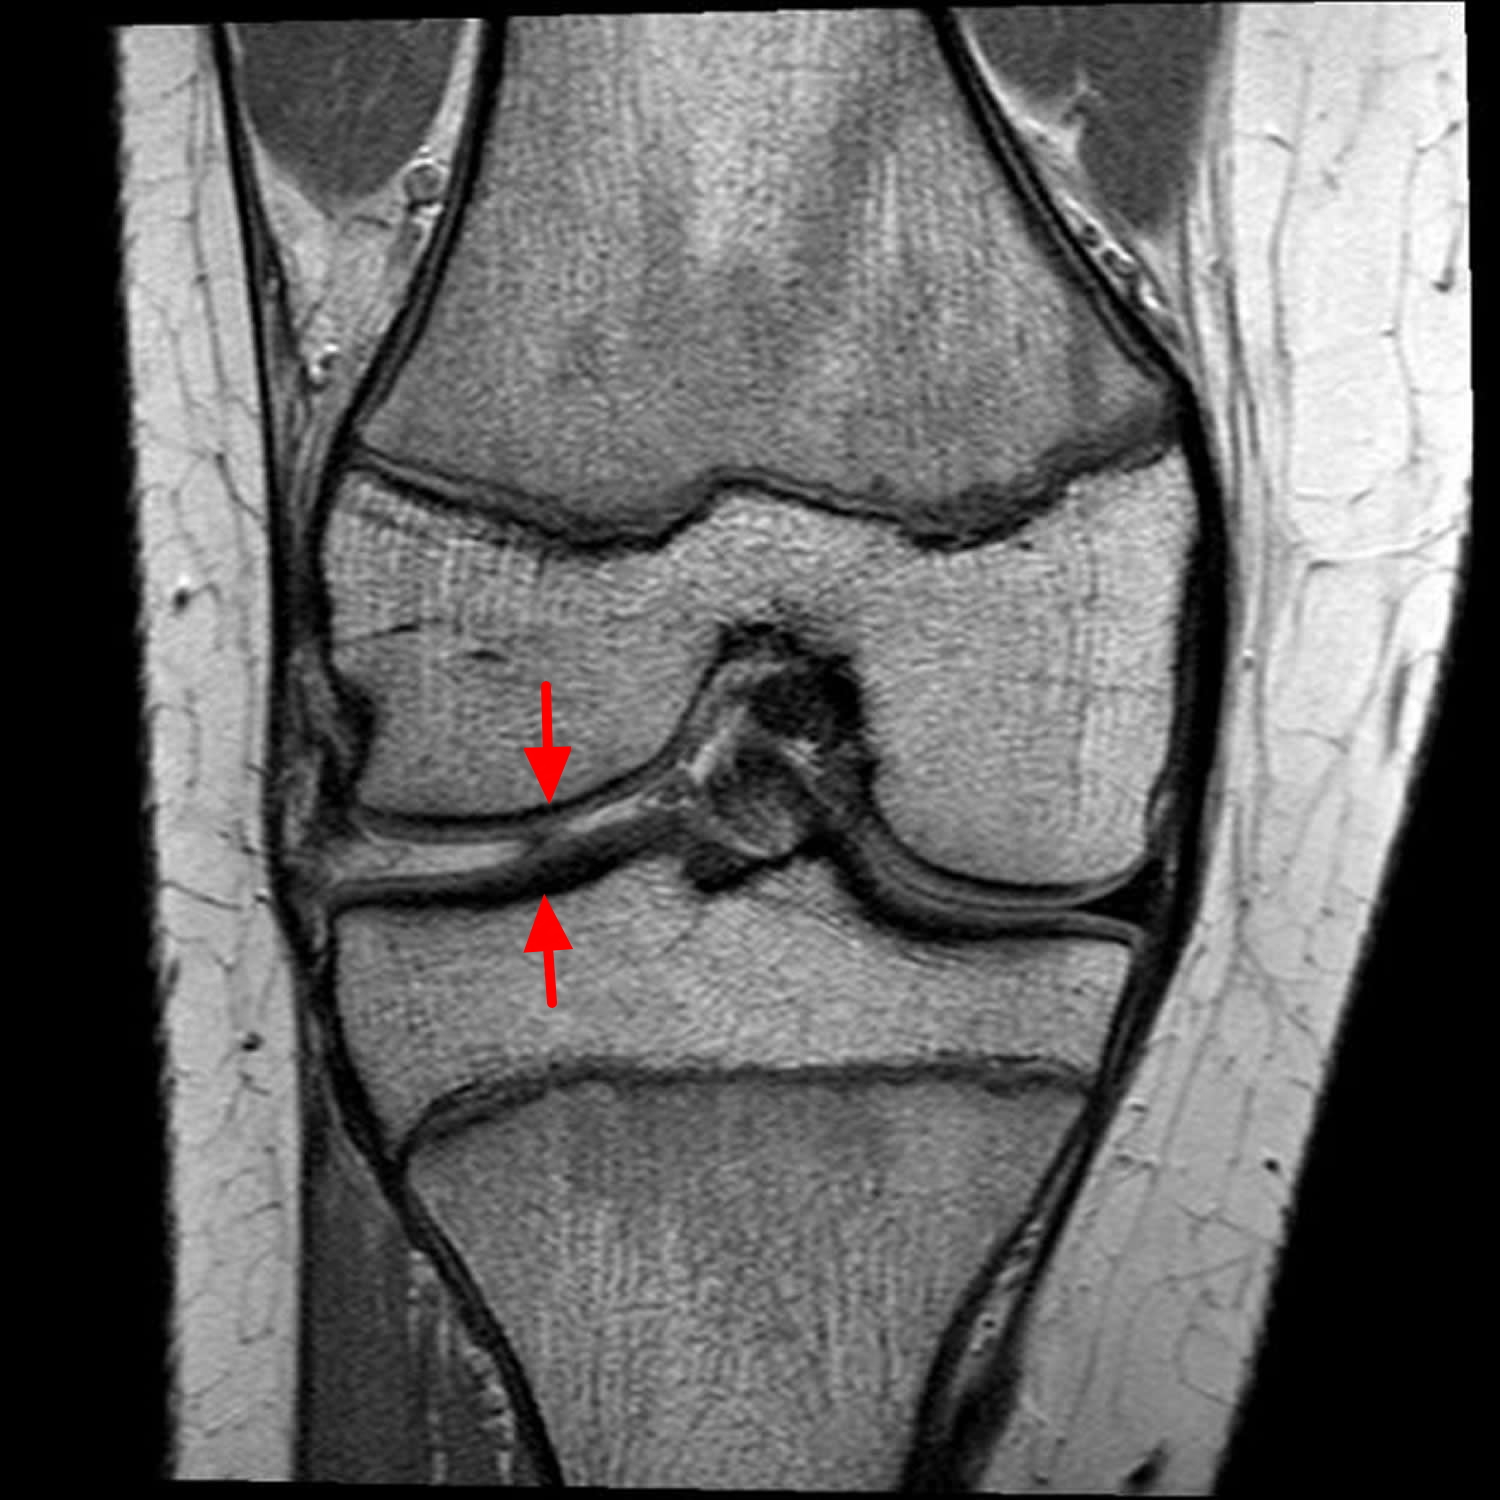

Suffering from an injury to lateral meniscus? Discover expert insights on common symptoms, effective diagnosis, and proven recovery options for this knee condition. Learn how to manage pain, explore physical therapy exercises, and understand when surgical intervention is necessary to regain full mobility and return to your daily activities safely. Proper care is essential for lasting joint health.

Read full article: Injury To Lateral Meniscus